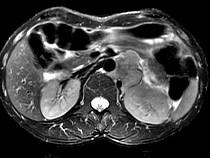

问题 男,54岁、1年前行胃癌切除术,现消瘦乏力、左锁骨上淋巴结肿大,影像检查如图,最可能的诊断是()

选项 A.淋巴瘤 B.腹膜后淋巴结转移 C.肾上腺腺瘤 D.肾上腺增生 E.腹膜后纤维肉瘤

答案 B